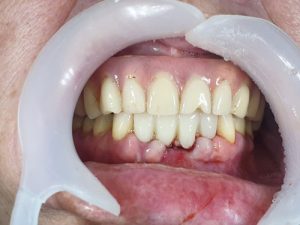

Assembly of the immediate load provisional bridge. Once the healing process is complete, the gums usually take the shape of the provisional bridge, if it is properly executed. Therefore, after this period, it is usually not necessary to modify anything and it is much simpler to proceed to the next step. Since immediate load was chosen, the crowns are not in occlusion, in order to reduce the pressure on the implants.

When performing immediate load and in the presence of specific dietary habits, doctors must adequately inform patients.